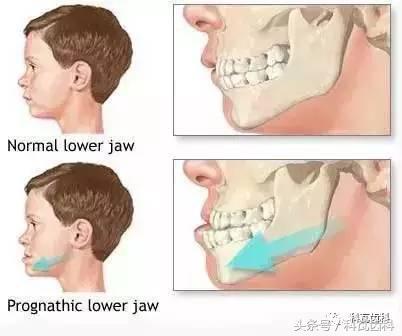

1、反牙合(地包天)

所谓的反牙合其实就是咱们通俗讲的“地包天”,就是下牙咬到了上牙的前方,所有的小朋友和家长一定要记住黄博士我说的话,如果这种情况一旦发生,原则只有六个字:早发现早调节。

千万别等啊!因为如果放任不管,后你的下巴会越长越大,越长越长。所以呢,小朋友3至5岁就可以找黄医生来看了,越早干预,你将来做手术整形的概率越低,因为反牙合放任不管的结果是像下面这样,现在又叫“香蕉脸”或“月牙脸”。